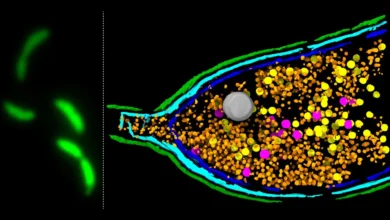

Stanford scientists discover “natural Ozempic” without side effects

Scientists at Stanford Medicine have identified a naturally occurring molecule that appears to mimic some of the weight loss effects…